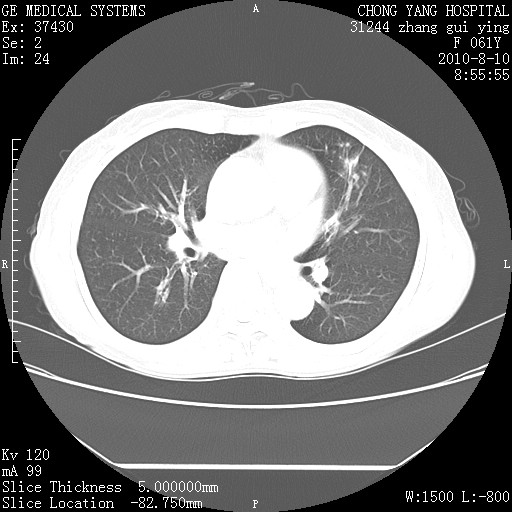

标题: CT28314:F61Y胸部增强,发热咳嗽一周入院,后面的为一周前平 [打印本页]

标题: CT28314:F61Y胸部增强,发热咳嗽一周入院,后面的为一周前平

1、支持考虑右侧中央型肺癌伴右肺中叶节段性不张及下叶支气管黏液痰栓    2、左肺上叶舌段感染。

我也觉得右肺中叶支气管受累

确切的说:1:右肺下叶中心型肺癌侵及中叶支气管并中叶不张,纵膈淋巴结转移。2:左肺舌叶炎症。3:右侧胸腔少量积液

右肺下叶内基底段近膈不规则肿块,考虑右肺下叶周围型肺癌可能性大。